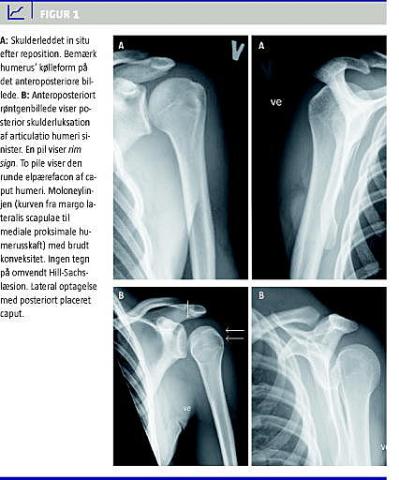

Posterior skulderluksation kan kompliceres af humerusfraktur, posterior skade på labrum (omvendt Bankartlæsion) samt kompressionsfraktur i den anteromediale del af caput humeri (omvendt Hill-Sachslæsion) [2]. Radiologisk kan caput humeri ses displaceret lateralt i forhold til den anteriore rand af cavitas glenoidalis. En forskydning på mere end 6 mm kaldes rim sign . Grundet indadrotation antager caput en »elpærefacon« (light bulb appearance ). Moloneylinjens konveksitet kan være brudt. En Hill-Sachslæsion ses som en vertikal linje på den mediale side af caput. Sammenholdt med mediale cortex ligner mellemrummet en rende (trough sign ) [2, 4]. Lateral optagelse viser caput beliggende posteriort for ledskålen. Aksiloptagelse skal foreligge ved mistanke om PS. Ved behov for supplerende billeddiagnostik er computertomografi (CT) relevant for at kortlægge associerede frakturer. Magnetisk resonans (MR)-optagelse er ikke nødvendig, idet isoleret rotatormanchetskade er uhyre sjælden ved posterior skulderluksation [2, 3].

En 19-årig mand stødte sin venstre skulder voldsomt mod en medspiller under fodboldspil. Patienten blev undersøgt og røntgenfotograferet på to forskellige skadestuer i løbet af de følgende to døgn. Tilstanden blev tolket som kontusion. På en tredje skadestue fandtes stærke smerter i venstre skulder. Der var breddeøget skulderregion, manglende fylde anteriort, og processus coracoideus føltes tydeligt. Armen lå i indadrotation og adduktion og kunne ikke bevæges fra denne position aktivt eller passivt. Neurovaskulære forhold var normale. Røntgen viste posterior skulderluksation (se Figur 1 ). I morfin- og stesolidrus foretog man reposition, hvorefter patienten kunne udadrotere. Røntgenkontrol blev tolket som skulderleddet in situ. Leddet blev bedømt til at være stabilt, hvorefter armen blev bandageret i indadrotation med fikseret mitella.